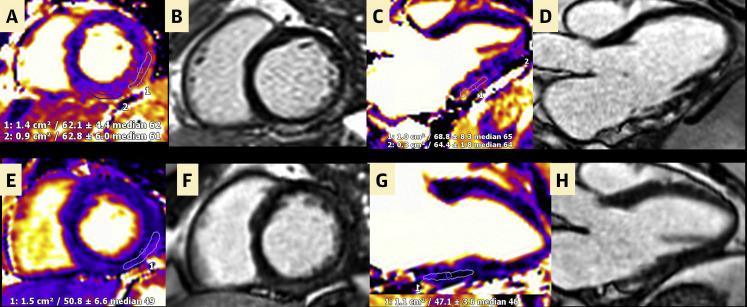

Cardiac Magnetic Resonance Imaging Midterm Follow Up of COVID-19 Vaccine-Associated Myocarditis.

JACC Cardiovasc Imaging. 2022 Oct;15(10):1821-1824. doi: 10.1016/j.jcmg.2022.01.008. Epub 2022 Mar 16.